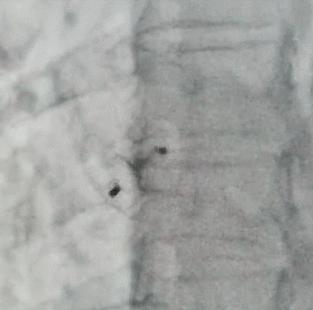

卵圆孔未闭的治疗并不复杂,穿刺大腿根部的股静脉插入心导管,将封堵器送到未闭卵圆孔,就可达到治愈目的。手术过程简单、安全、可靠,并发症罕见,整个手术过程仅需 20-30 分钟。术后第一天可下床活动。术后 3~6 个月内皮组织就完全覆盖封堵器。与冠心病不同,一般术后不需要长期服药,仅服用阿司匹林6个月,术后应定期复查心脏超声及右心声学造影。